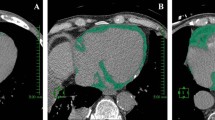

Epicardial fat measurement

Dedicated semi-automated software was used to quantify the volume of epicardial fat. In the non-contrast CT data sets, the pericardium was automatically segmented after estimating cardiac orientation and aligning a heart model [30]. If necessary, contours of the pericardium could be corrected by the reader. As a result, a volume of interest (VOI) delineating the pericardial sac was obtained. The fat content inside the VOI was then isolated using HU thresholding, which was visually adjusted by the user to ensure that all adipose tissue within the pericardial sac was included.

Regarding biomarkers EFV was significantly associated with MCP-1 (P = 0.037) and IP-10 (P = 0.002) (Fig. 1; Table 2) while CAC was significantly correlated with G-CSF (P = 0.016) and IL-13 (P = 0.041) (Table 2). Other biomarkers showed no associations with EFV and CAC in this study. In multivariable analysis IP-10 (values >150 pg/mL) remained as the only predictive biomarker for High-EFV with an odds ratio of 1.68 (95 % CI 1.05; 2.68; P = 0.029). Regarding traditional risk factors, obesity (OR 5.08; CI 2.65; 9.75; P < 0.001), male gender (OR 3.25 CI 1.92; 5.51; P < 0.001), hypertension (OR 2.71; CI 1.63; 4.51; P < 0.001), age >60 years (OR 1.95, CI 1.19; 3.18; P = 0.008) and smoking (OR 1.93; CI 1.20; 3.11, P = 0.007) were significantly associated with high epicardial fat in multivariable analysis (Fig. 2).